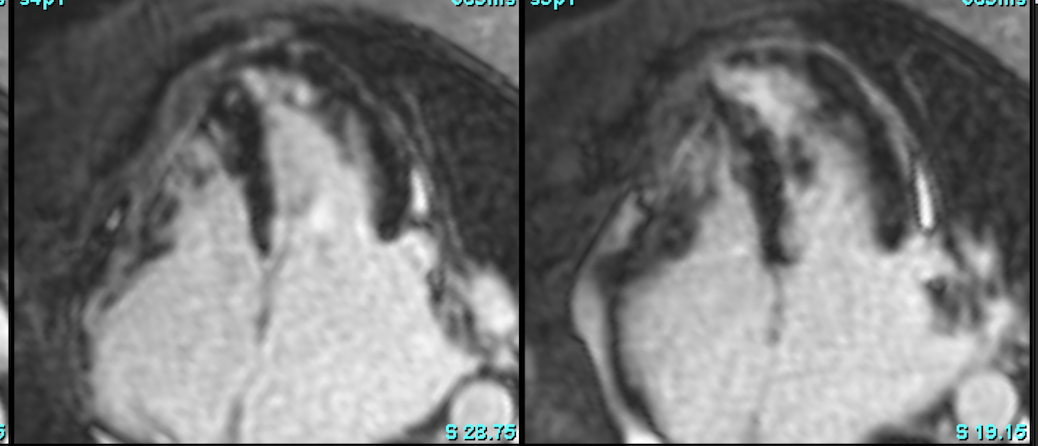

Cardiac MRI is a useful tool to diagnose amyloidosis. T1 mapping has become a mainstay, both native and ECV measurements. ECV measurement can now help quantify the amyloidosis burden and may help guide treatment based on how the ECV responds to specific treatment measures.

RVoTo involvement in HCM is uncommon but diagnosing it may change the management plan and prognosis